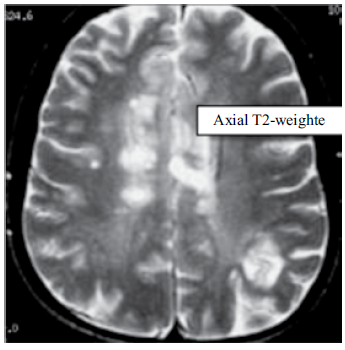

Paciente do sexo feminino, com 35 anos de idade, apresenta a ressonância magnética a seguir.

A hipótese diagnóstica é